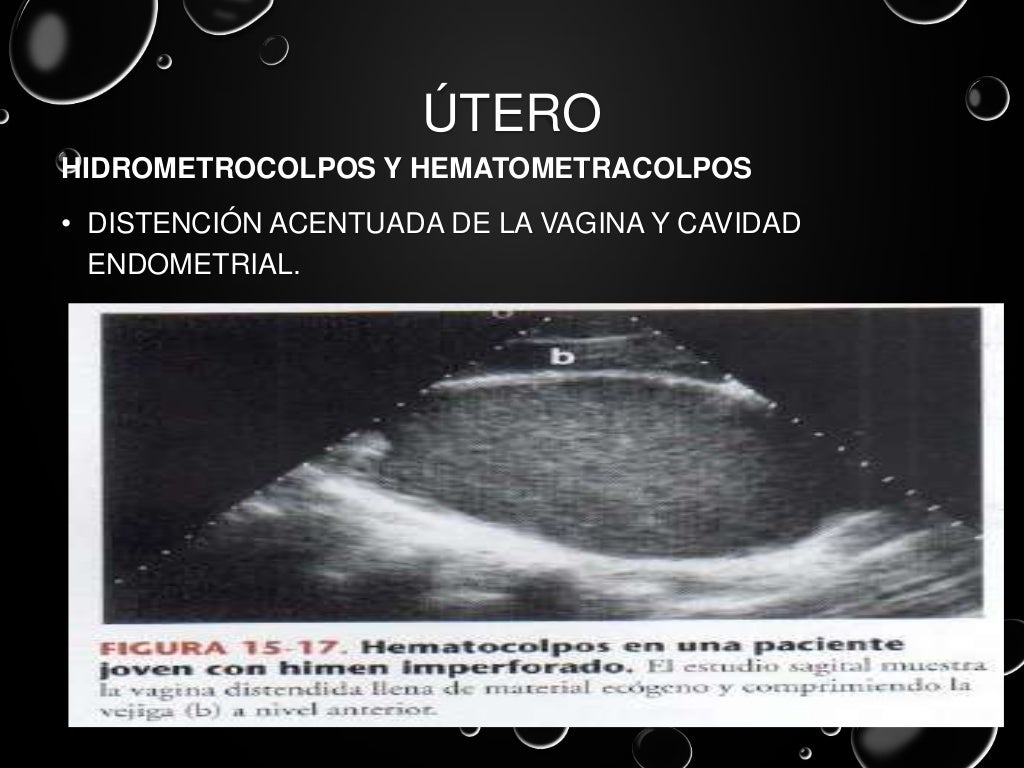

Ultrasonido pelvico

Source: es.slideshare.net